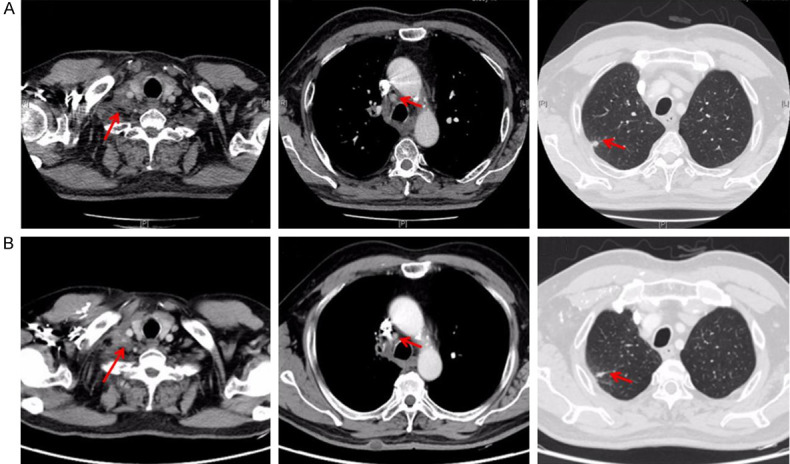

As the treating mode in Gemstone 301 study or Pacific study, the subsequent PD-1 or PD-L1 inhibitor should be administrated in consolidation treatment for unresectable stage III NSCLCs after cCRT or sCRT. While this patient had a history of autoimmune disease psoriasis and immunotherapy non-response associated STK11 and TP53 mutations, immune checkpoint inhibitors (ICIs) might be not suitable for this patient, in case of the occurrence of uncontrolled immune-related adverse effects and immunotherapy super-progression. Considering rapid resistance to chemotherapy after the first 2 cycles, maintenance therapy was indispensable for him. Antiangiogenic consolidation therapy was a good recommendation according to locally advanced subgroup of the Beyond study [5]. Since this patient had a history of grade 3 hypertension, Bevacizumab was not suitable because of its adverse effect of exacerbating hypertension. Thus, during the 19 months of Endostar administration, the patient was recommended to receive 23 cycles consolidation therapy of Endostar with 210 mg continuous infusion for 72 hours per 21 days from July 8, 2021 to Feb 10, 2023. Imaging evaluation including enhanced chest CT, enhanced Brain magnetic resonance (MR), abdominal CT, pelvic CT and cervical ultrasound, was administrated per 3 cycles. Whole body bone imaging was reviewed twice a year. The evaluation was always stable disease (SD) with no new lesion or enlarged lesion detected during the follow-up (Figure 4). The date of the latest follow-up was Dec 19, 2022. The progression-free survival (PFS) of Endostar consolidation therapy has exceeded 17 months. Clinical course including treatment process and relevant assessment was shown in Figure 5.

Figure 4.

Radiological appraisal after Endostar consolidation treatment. A. Chest CT scan before Endostar consildation treatment on July 1, 2021. B. Chest CT scan after 17 months follow-up of Endostar consildation treatment on Dec 19, 2022.